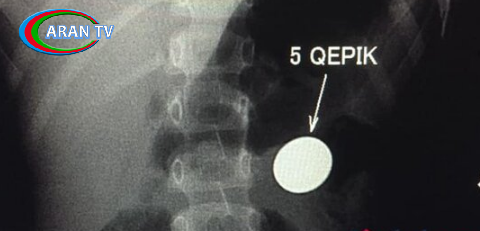

Bakıda 4 yaşlı uşağın mədəsində qəpik AŞKARLANDI

“Bir həftə qabaq 4 yaşında uşaq 5 qəpik udub. Bir həftədir qəpik uşağın mədəsindən ifraz olunmur. Gətiriblər müayinəyə, biz də aşkar etdik ki, qəpik hələ mədədir. Mədənin çıxacaq hissəsi uşaqlarda dar olduğuna görə çıxmır. Qəpiyin diametri mədənin çıxacaq hissəsinin diametrindən iki dəfədən çox böyükdür. Ona görə mədədən keçmədi, qalıb mədədə. Biz məsləhət gördük ki, endoskopiya müayinəsindən keçsin, endoskopik yolla çıxartsınlar. Hələ bir xəbər yoxdur. Qəpik uşağın mədəsindən çıxarılacaq”.